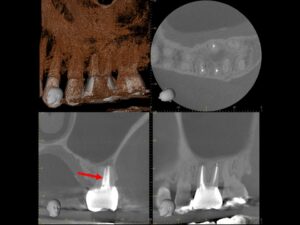

同CT画像。ファイバーコアで土台を補強し、仮歯の状態で3か月の経過観察を行った。初診時にあった歯の違和感は完全に消失したため、オールセラミックで補綴処置を行うこととした。